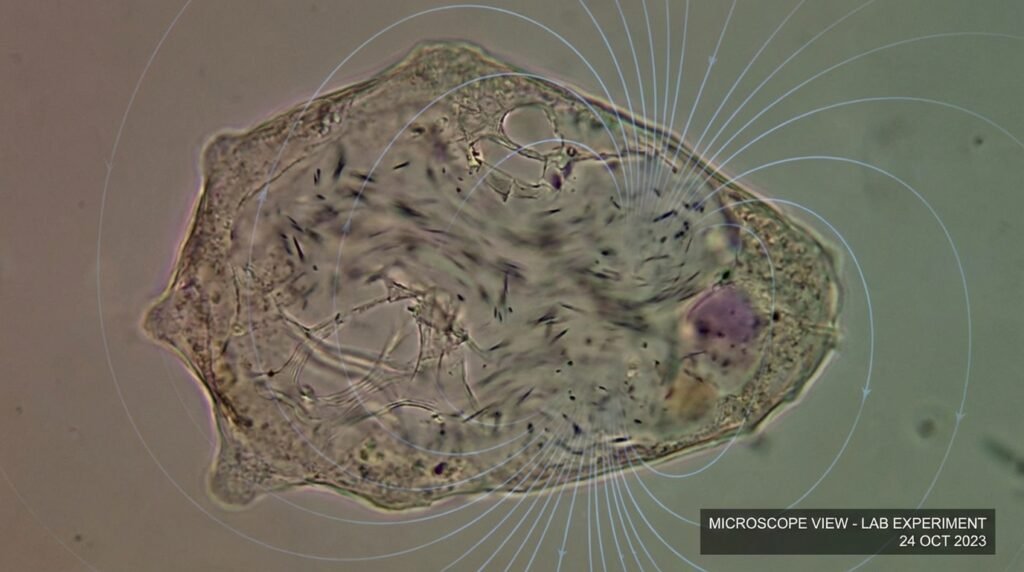

Every malaria parasite contains a small compartment packed with microscopic iron crystals called hemozoin and the scientists discovered that the crystals move continuously throughout their environment because they exhibit spinning and bouncing and colliding behavior which resembles “rocket engine” operation at a microscopic level.

Researchers observed that crystal spinning stops immediately after a malaria parasite dies and scientists use this motion as a “heartbeat” to determine parasite life status while measuring drug effectiveness against parasitic infections.